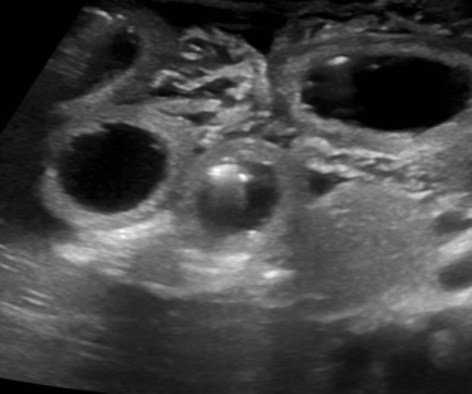

L’ecografia addome (Figura 2) eseguita in urgenza, invece, rilevava una marcata distensione di anse del tenue in emiaddome destro, con pareti ispessite e iperemiche, e un marcato ispessimento della radice del mesentere adiacente, che risultava dislocato al fianco destro.

Gli aspetti ecografici e l’età del piccolo paziente indirizzavano pertanto la diagnosi verso un volvolo del tenue su probabile malrotazione. Il bimbo veniva pertanto trasferito presso il reparto di Chirurgia Pediatrica, dove veniva sottoposto a intervento di derotazione di matassa intestinale convoluta, resezione di tratto intestinale ileale e anastomosi termino-terminale intestinale.